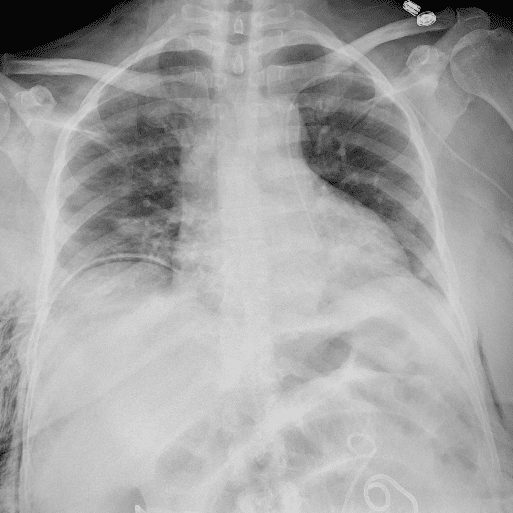

Practice Cases